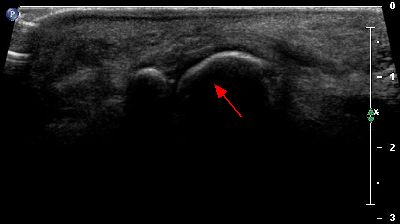

Lesioni legamentose

Lesione legamento peroneo-astragalico anteriore Lesione legamento peroneo-astragalico anteriore